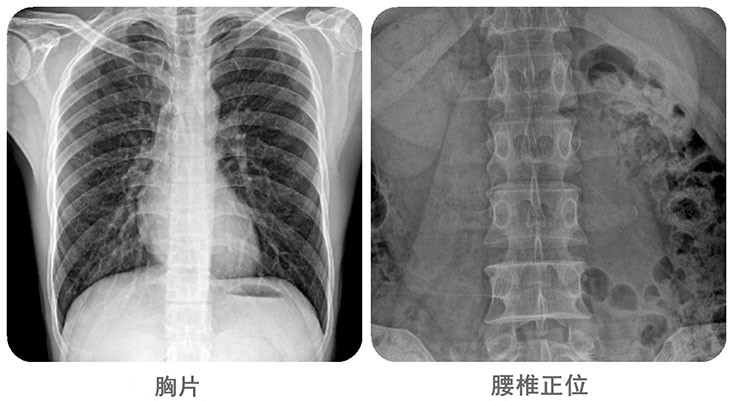

清晰影像,便于臨床診斷。移動DR能夠滿足人體的頭部、四肢、胸腔、脊柱、腰椎、腹部等全身多部位的數字化攝影需求。